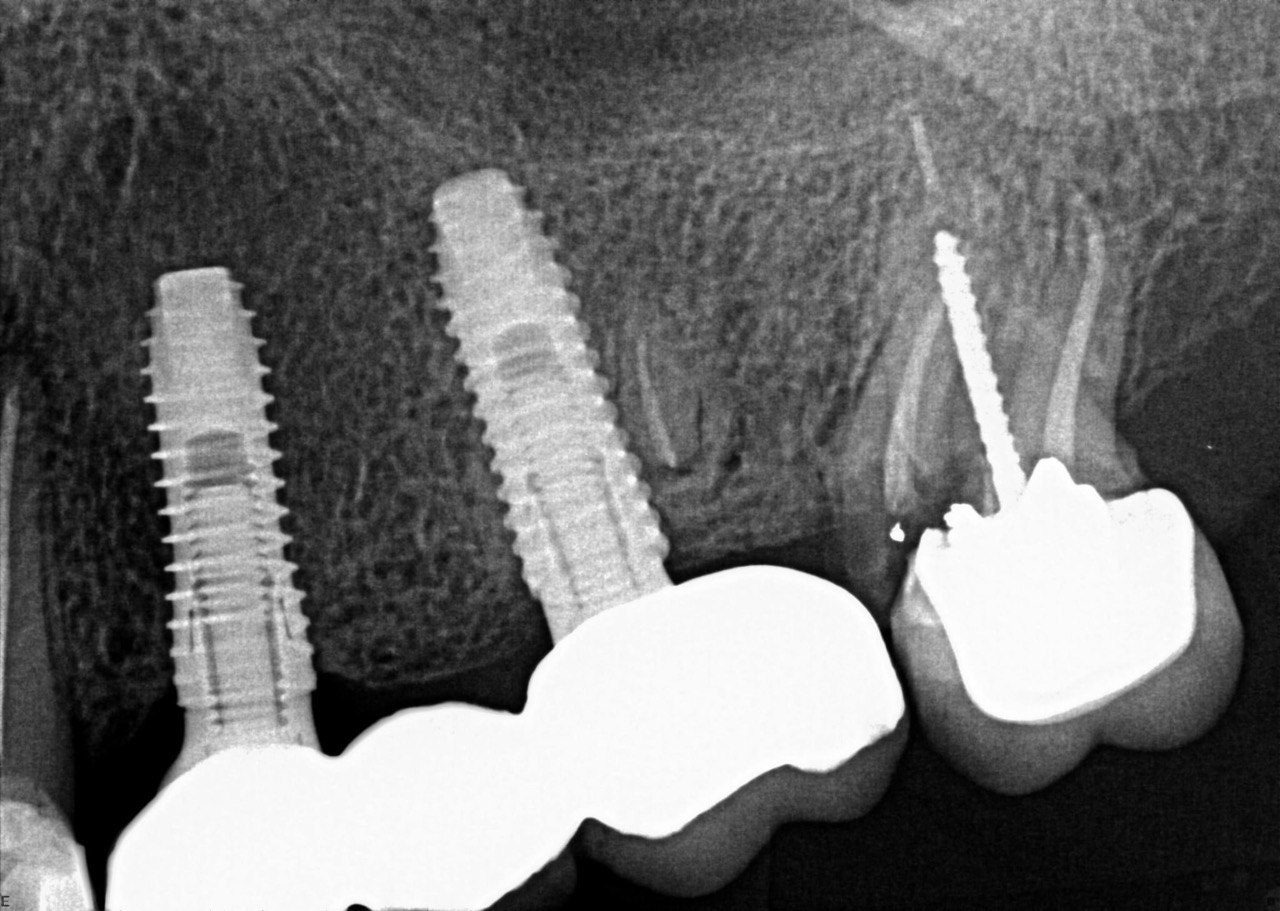

1. What option can be selected regarding the implant seen in this X ray?

2. What option can be selected regarding the implant seen in this X ray?

3. What option can be selected regarding the implant seen in this X ray?

4. What option can be selected regarding the implant seen in this X ray?

5. What option can be selected regarding the implant seen in this X ray?

6. What option can be selected regarding the implant seen in this X ray?

7. What option can be selected regarding the implant seen in this X ray?

8. What option can be selected regarding the implant seen in this X ray?

9. What option can be selected regarding the implants seen in this X ray?

10. What option can be selected regarding the implant seen in this X ray?

11. What option can be selected regarding the implant seen in this X ray?

12. What option can be selected regarding the implants seen in this X ray?

13. What option can be selected regarding the implants seen in this X ray?

14. What option can be selected regarding the implants seen in this X ray?

15. What option can be selected regarding the implants seen in this X ray?

16. What option can be selected regarding the implants seen in this X ray?

17. What option can be selected regarding the implants seen in this X ray?

18. What option can be selected regarding the implants seen in this X ray?

19. What option can be selected regarding the implants seen in this X ray?

20.What option can be selected regarding the implants seen in this X ray?